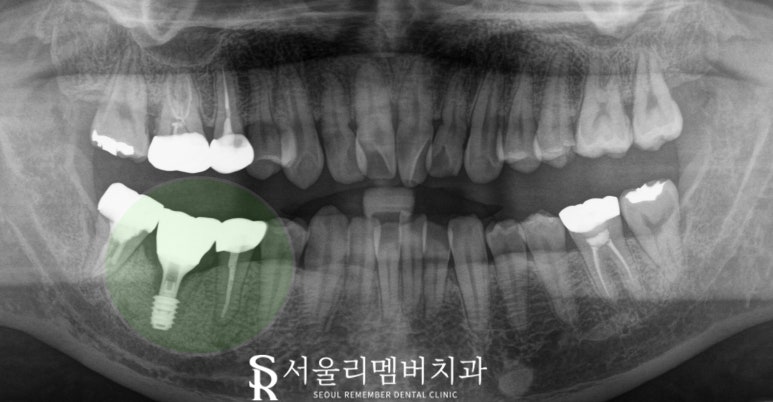

46번은 치아를 뽑고

임플란트를 심은 뒤

몇 개월 동안 기다려 되기에

상대적으로 기간이 더 오래 걸리는 것을 감안하여

식립 수술을 먼저 진행했습니다.

서울대입구역 치과 에서는

염증으로 인해 뼈의 상태가 좋지 못한 것을

고려하여

오스템의 SOI 제품을 심었는데요,

초친수성 표면으로

혈병 형성을 촉진하여

골유착을 빠르게 하고

치료 기간을 단축시키는 장점이 있는

픽스처를 사용했습니다.

당뇨, 고혈압 같은 전신질환이 있거나

얇거나 약한 잇몸뼈, 고령화로 약해진 잇몸을

가진 경우에 적합합니다.

모든 진료를 마친 모습을 보면

뼈가 녹고 염증이 가득했던 구치부가

건강을 회복한 것을 볼 수 있습니다.

워낙 뼈 상태가 좋지 못해서

깊게 심을 수밖에 없었지만

환자 개인 맞춤형 어버트먼트를 이용해

이러한 한계도 잘 극복해 드렸으며

교합관계 체크 및

인접면 컨택 공간도 꼼꼼하게 확인 후

마무리해드렸습니다.